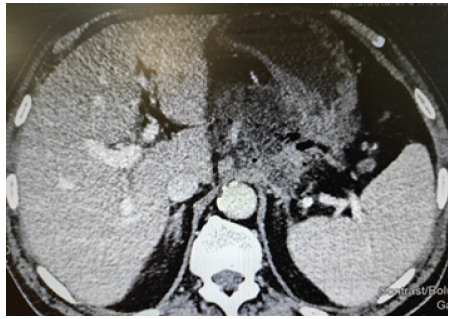

On the CT the necrosis of pancreas can be visualized at least 72 h after the beginning of this complication. This is the optimum time for initial CT scan (Figure 1) [3].

3. If peripancreatic fluid collections are homogenous that persist beyond 4 weeks are described as pseudocysts. Usually we apply mini-invasive approach for treatment [2,4] (Figure 1).